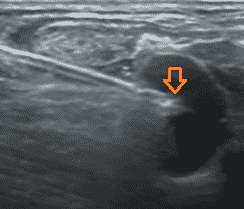

Muchos estudios han demostrado que la técnica ecoguiada para colocar dispositivos venosos totalmente implantados es segura y eficaz. Es hoy en día, un recurso indispensable que mejora de forma considerable el éxito en la primera punción y reduce drásticamente los riesgos relacionados con la misma.

La técnica con ultrasonido se ha convertido en el método de rutina para el cateterismo de la vena yugular interna (VYI) reduciendo drásticamente las tasas de fracaso y complicaciones para la colocación del reservorio venoso.

De hecho, una vez controlada la técnica el porcentaje de éxito en la primera punción es cercano al 100%. Cobra especial importancia la consulta preoperatoria que permite a través de un reconocimiento venoso del trayecto que tendrá el catéter, elegir la vena correcta y descartar las que no se pueden pinchar o las que darían problemas.

2. Fundamentos ecográficos a conocer para acceder a la vena

Existen 2 técnicas principales:

- Out of plane: fuera de plano o plano transversal

- In plane: en plano o plano longitudinal

En ciertos casos es posible usar una técnica que combina las 2 anteriores: se trata de un tener una aproximación longitudinal de la aguja en un plano transversal: